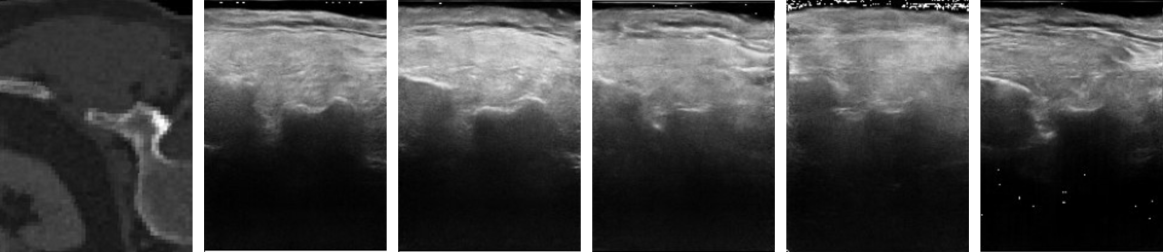

Figure 4: Qualitative evaluation of ultrasound (US) simulation. (left) Evaluation with the testing dataset. The top row shows 2D CT slices of the human specimen. The corresponding real US and the generated US of Sonogym are shown in the rows below. (right) Examples of simulated US images in SonoGym. Sliced CT, model-based (MB) US simulation, and learning-based US simulation are shown in the top, middle, and bottom rows, respectively. The learning-based US simulation has high visual similarity to real US images.

Q1: How realistic and efficient is the ultrasound simulation? Fig. 4 presents a qualitative evaluation of the ultrasound images generated by our pix2pix network. Fig. 4 (left) shows that our network can simulate realistic images during testing. Fig. 4 (right) provides examples of both model-based (MB) and learning-based (LB) ultrasound simulations. Our LB approach maintains high visual quality despite the domain gap between the input CT slices and the training CT data. For quantitative metrics, we achieve LPIPS loss of 0.24150.24150.24150.2415, SSIM score of 0.39400.39400.39400.3940, and PSNR score of 15.9615.9615.9615.96, which is close to the performance of similar works reported in dominguez2024diffusion . On an RTX 3090 Ti, the parallel rendering of ultrasound images with size 200×150200150200\times 150200 × 150 of 100 environments takes 0.00890.00890.00890.0089 and 0.11070.11070.11070.1107 seconds for MB and LB approaches, respectively. This enables training high-performing PPO agents within approximately 2 hours for MB simulations and 10 hours for LB simulations.